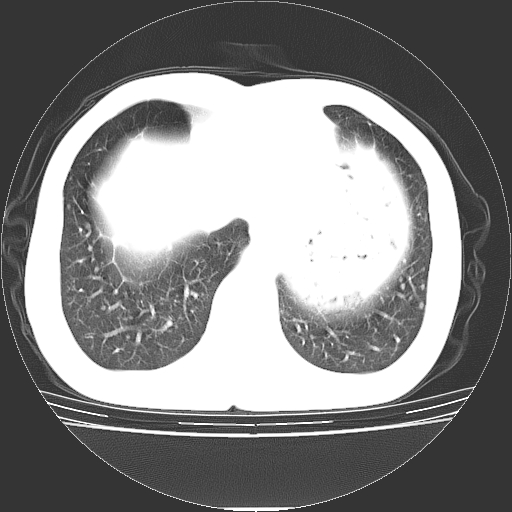

以下是引用yangyudong333在2008-4-29 5:38:00的发言:[br]比较典型的矽肺结节.支持[br]诊断依据:[br] 1.x线表现:[br] ①典型矽肺为多发直径 1~3mm 小结节,即矽结节,由胶原纤维和硅尘构成,可融合成团块,好发于上肺。[br] ②团块周围常有肺大泡。[br] ③胸内淋巴结增大、钙化。如肺门淋巴结呈蛋壳样钙化有助于与其他尘肺区别。[br] ④胸膜常广泛粘连、增厚。[br] 2.ct表现[br] ①两肺散在大小较为一致的小结节影,其密度较高,边界清楚。[br] ②小结节可融合为较大团块影,直径约 1cm ,甚至可达 10cm以上,易发生在上叶。[br] ③小结节周围常并有小叶中心气肿或弥漫性肺气肿。

以下是引用liuyue在2008-4-28 22:30:00的发言:[br]比较典型的矽肺结节.[br]请结合临床及化验除外矽肺合并肺结核之可能.